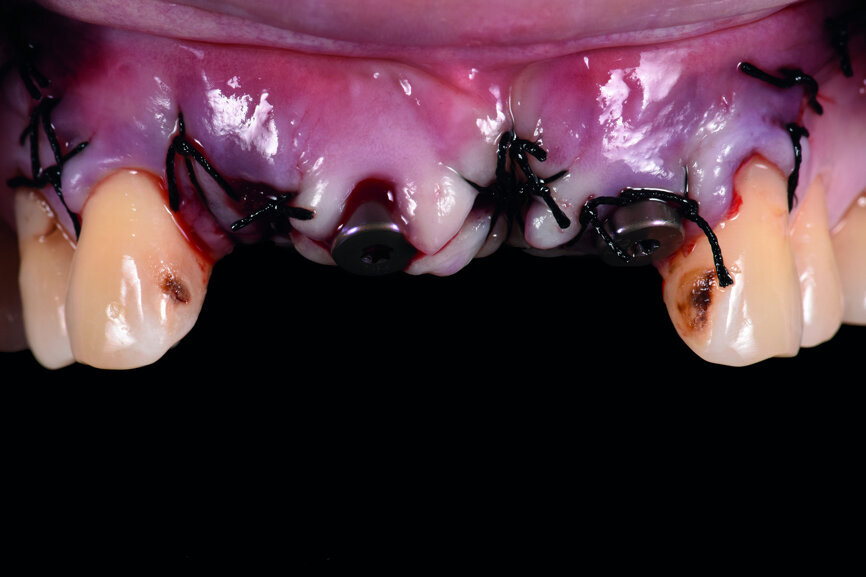

Fig. 5: Frontal view of the anterior teeth immediately post-op.

Teeth #12, 21 and 22 were extracted. Tooth #11 underwent early implantation and tooth #22 immediate implantation with GBR (Figs. 5 & 6). After three months of healing, osseointegration had taken place. An implant level impression was taken for fabricating a provisional bridge supported by temporary abutments for teeth #12–22. The technician modified the shape of the artificial gingiva on the model in order to form the proper gingival curve and emergence profile, then finished the provisional bridge, while the dentist modified the gingival shape using an olive-shaped bur intraorally (Figs. 7–18).

Three weeks later, after a general physical check-up, implantation was begun. Usually, operation within 48 hours after tooth extraction is considered as immediate implantation, while operation within the first six weeks after tooth extraction is considered as early implantation. Therefore, in this case, implant #11 was early implantation and implant #22 immediate implantation. The preoperative CT analysis showed that the labial side of the alveolar ridge of teeth #12, 11 and 22 was deficient; thus, GBR was needed in order to obtain sufficient bone quantity.